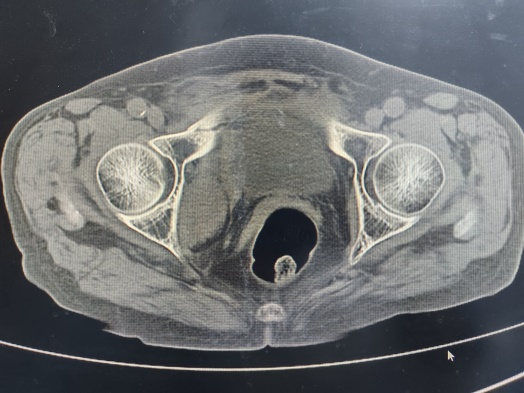

图3:老年骨盆脆性骨折诊治流程